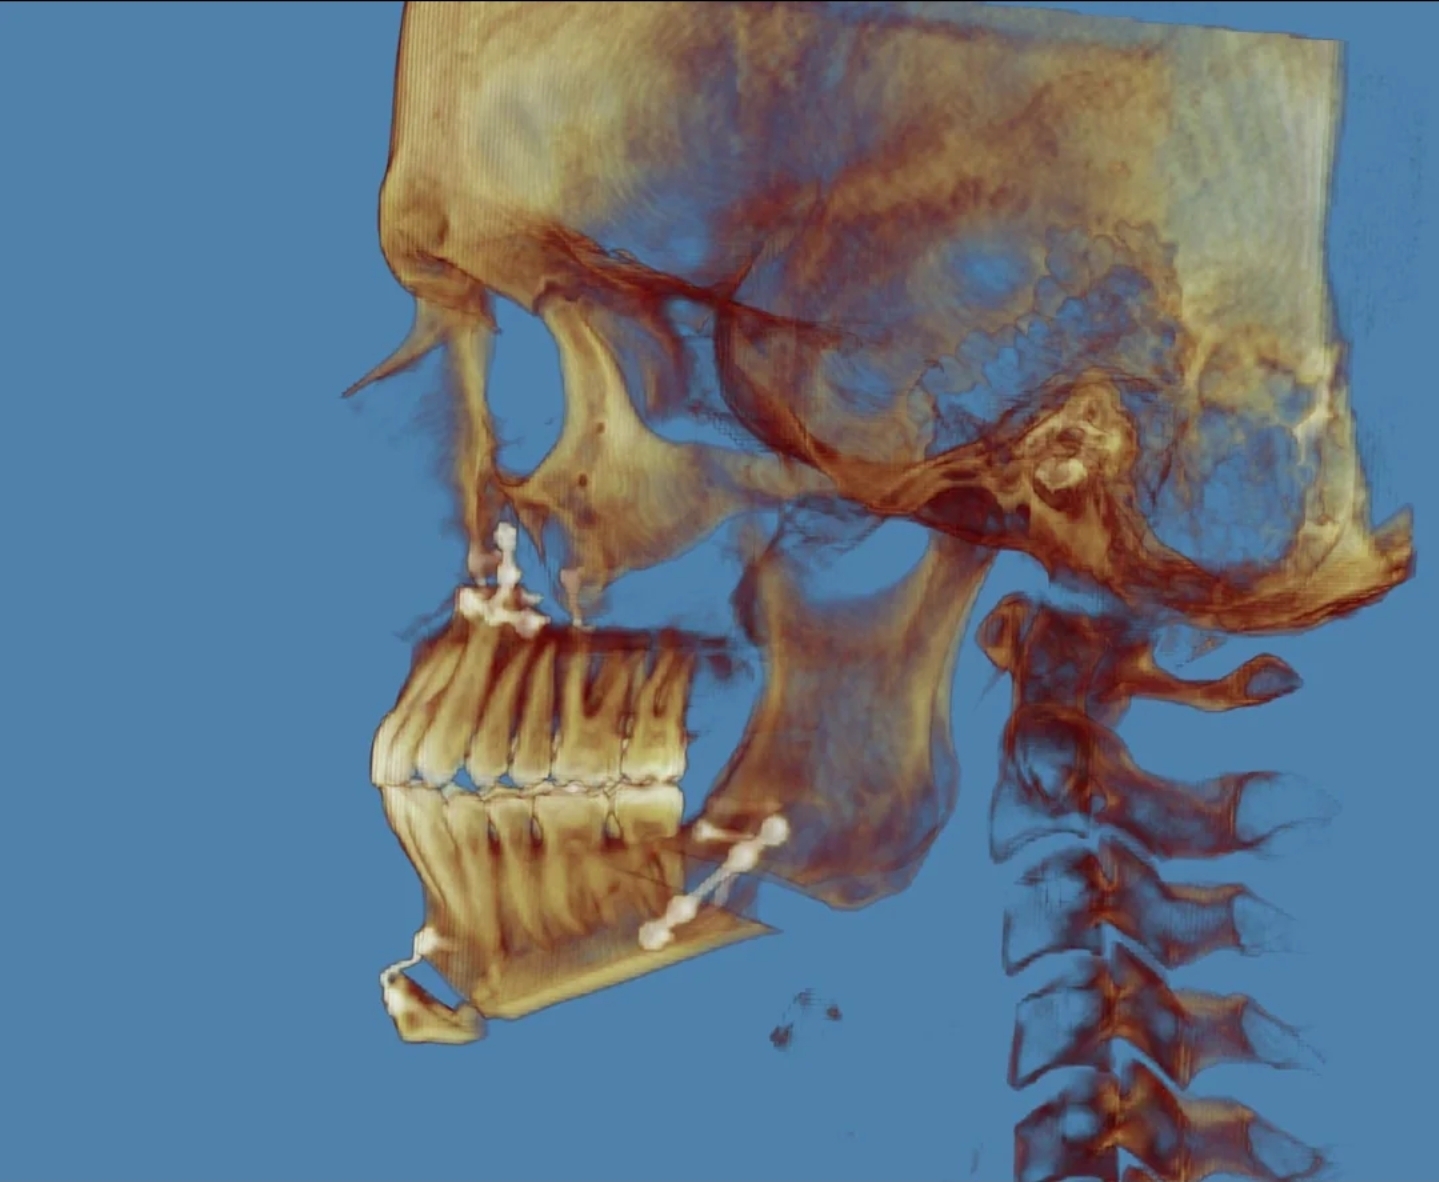

Its when you overotate, when you overrotate, ans(nose base) comes back, and with that the upper lip. He could have also created a bigger overbiteView attachment 4410584

subspinal could have been a good choice for himNah its the genio, its a low cut genio that wont change lips much. He was overotated and the maxilla should have moved forward compared to the bsso.

He should have done less ccw and less bsso. Maybe he decomped lower jaw to much relative to the upper jaw aswell. Unfortunately many people just wants as much ccw and bsso as possible but they dont think of this riskssubspinal could have been a good choice for him